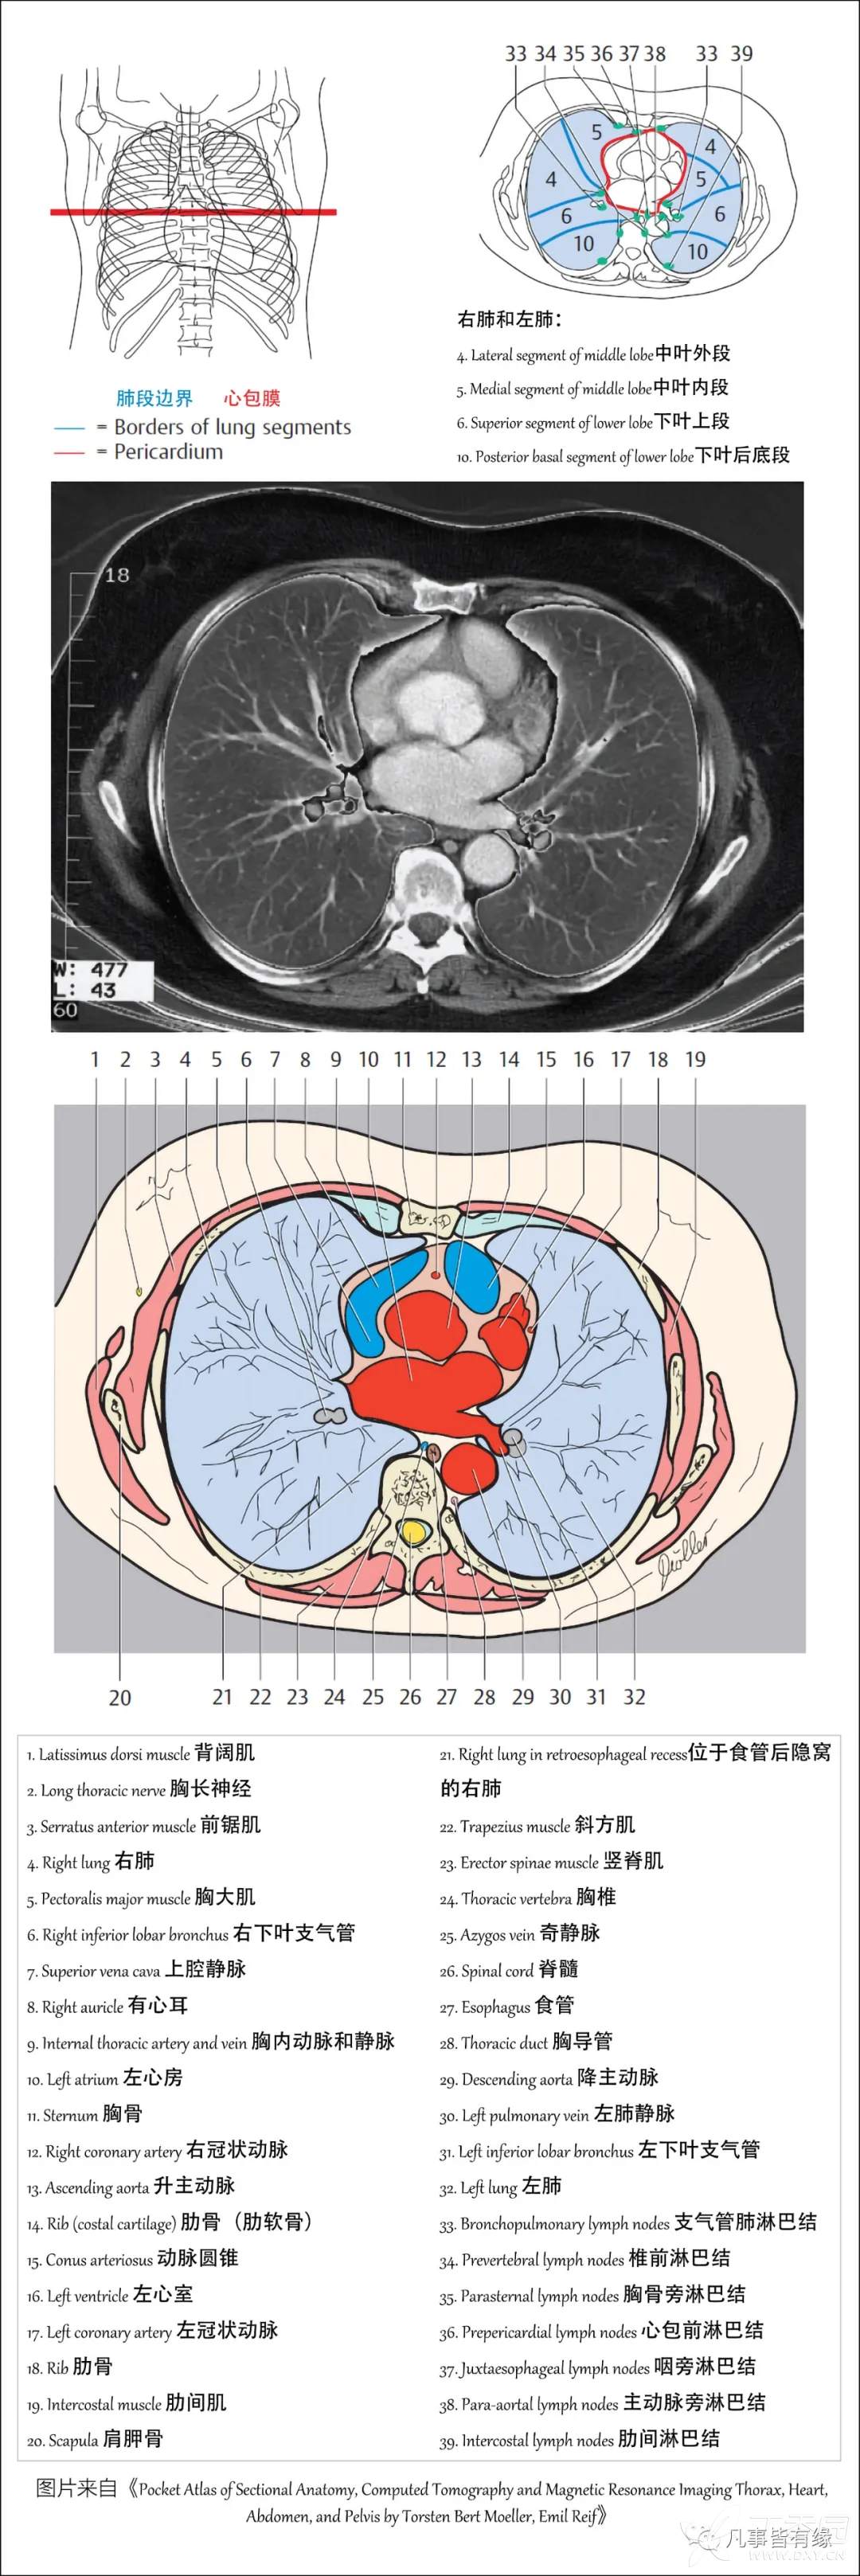

(一)胸部CT轴位断层解剖: